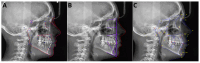

Background: Cephalometric analysis (CA) is an indispensable diagnostic tool in orthodontics for treatment planning and outcome assessment. Manual CA is time-consuming and prone to variability. Methods: This study aims to compare the accuracy and repeatability of CA results among three commercial AI-driven programs: CephX, WebCeph, and AudaxCeph. This study involved a retrospective analysis of lateral cephalograms from a single orthodontic center. Automated CA was performed using the AI programs, focusing on common parameters defined by Downs, Ricketts, and Steiner. Repeatability was tested through 50 randomly reanalyzed cases by each software. Statistical analyses included intraclass correlation coefficients (ICC3) for agreement and the Friedman test for concordance. Results: One hundred twenty-four cephalograms were analyzed. High agreement between the AI systems was noted for most parameters (ICC3 > 0.9). Notable differences were found in the measurements of angle convexity and the occlusal plane, where discrepancies suggested different methodologies among the programs. Some analyses presented high variability in the results, indicating errors. Repeatability analysis revealed perfect agreement within each program. Conclusions: AI-driven cephalometric analysis tools demonstrate a high potential for reliable and efficient orthodontic assessments, with substantial agreement in repeated analyses. Despite this, the observed discrepancies and high variability in part of analyses underscore the need for standardization across AI platforms and the critical evaluation of automated results by clinicians, particularly in parameters with significant treatment implications.